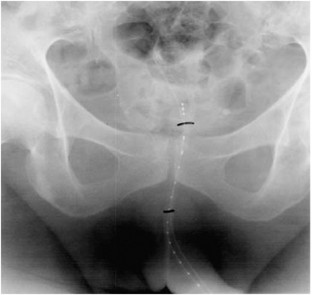

Advanced prostate cancer patients frequently deal with intractable prostatic bleeding which is a difficult problem to manage. Intraurethral high-dose rate (HDR) brachytherapy may palliate this condition. Advanced prostate cancer patients with intractable prostatic bleeding were offered brachytherapy with Iridium-192 using a Micro-selectron HDR machine. During a 5-year period, analysis was performed in 23 patients with a median age and Gleason score of 78 years and 9, respectively. Following brachytherapy, haematuria resolved in 19 of the 23 patients and was recurrence free at 6 months. Intraurethral HDR brachytherapy is a potentially effective modality for treating haematuria in patients with advanced prostate cancer.

Thurairaja, R., Pocock, R., Crundwell, M. et al. Brachytherapy for advanced prostate cancer bleeding. Prostate Cancer Prostatic Dis 11, 367–370 (2008). https://doi.org/10.1038/pcan.2008.12